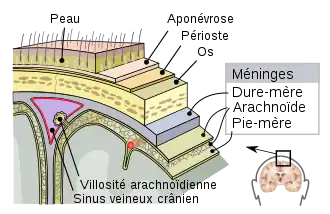

Contrairement aux feuillets plus externes (arachnoïde et dure-mère) qui suivent l’endocrâne, la pie-mère dans sa partie cranienne épouse étroitement le relief du parenchyme en suivant les sillons, scissures et circonvolutions du cortex cérébral, ce qui fait que sa surface est beaucoup plus importante que celles des autres méninges qui sont tendues au-dessus des renfoncements du tissu nerveux. Les espaces ainsi formés entre la pie-mère et l’arachnoïde sont appelés espaces sous-arachnoïdiens ; certains sont plus largement dilatés en ce qu’on appelle des citernes sous-arachnoïdiennes, elles sont situées à la base du crâne principalement autour du tronc cérébral. Les espaces sous-arachnoïdiens sont remplis de liquide cérébrospinal anciennement appelé liquide céphalo-rachidien (LCR) et traversés par des trabéculations ou travées arachnoïdiennes qui attachent la pie-mère à la face interne de la membrane arachnoïde.

La pie-mère forme, avec la membrane arachnoïde, la leptoméninge (du grec leptos « mince » « faible » et mênigx « méninge ») ; - structurel : avec des tissus spécialisés : les ligaments denticulés attachent la pie-mère spinale à la dure-mère en passant à travers l’arachnoïde ; le filum terminal ou « queue-de-cheval » qui prend la forme de filaments parallèles à partir du cône médullaire à l’extrémité caudale du rachis.

Une coupe des différents méninges.

Représentation schématique d'une coupe du haut du crâne, montrant les membranes du cerveau. Coupe schématique du cuir chevelu.

Coupe schématique du cuir chevelu.